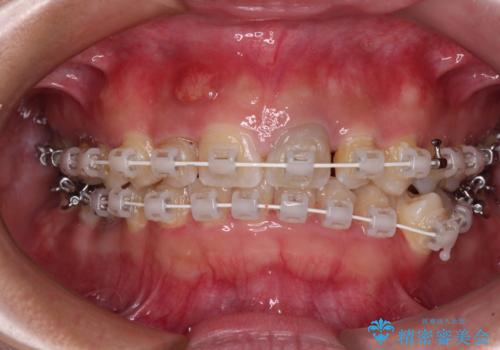

- 矯正装置

- 審美装置

矯正治療は、小臼歯1本分を歯列に納めないいけない状態であったため、表側のワイヤー装置にて行うこととしました。

下顎の小臼歯を移動しきるのに2年弱の期間を要することとなり、補綴治療も合わせて2年半ほどの治療期間となりました。